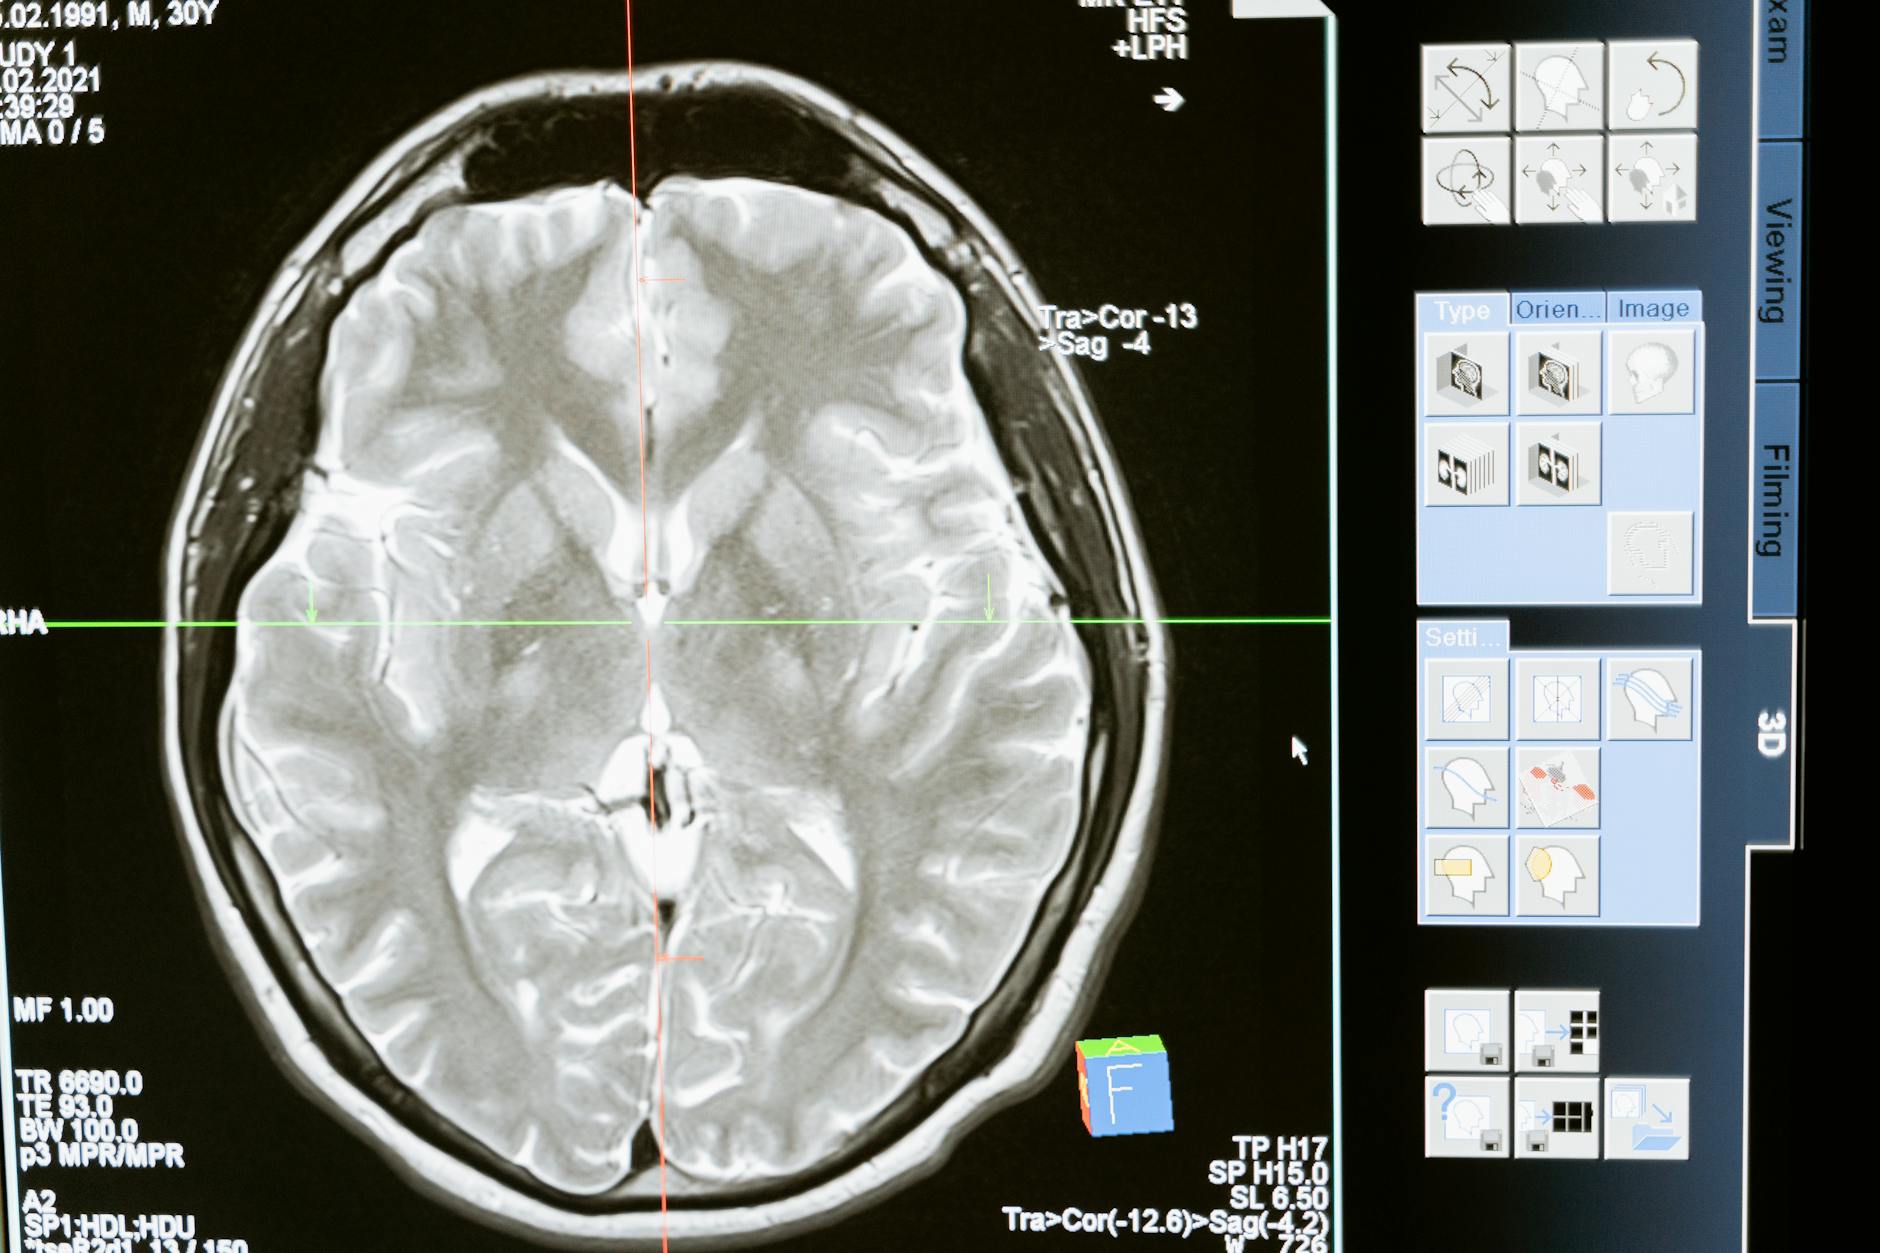

For people living with dementia or caring for someone who is, this question carries extra weight. Statins have been studied extensively for potential neuroprotective effects, and the two drugs differ in how they interact with the brain. Atorvastatin is lipophilic, meaning it crosses the blood-brain barrier more readily, while rosuvastatin is hydrophilic and largely stays out of the central nervous system. Whether that distinction matters for cognitive outcomes is still debated, and we will dig into that research below. This article also covers how each drug performs on LDL lowering, side effect profiles including the muscle pain that plagues many statin users, drug interactions that matter for older adults on multiple medications, cost considerations, and what the emerging evidence says about statins and brain health.

The relationship between statins and cognitive health is one of the more confusing areas in modern medicine. The FDA added a warning to all statin labels in 2012 about reports of memory loss and confusion, which understandably alarmed patients and caregivers. However, multiple large observational studies and meta-analyses conducted since then have generally found that statins do not increase dementia risk, and some research suggests they may be modestly protective. The distinction between atorvastatin and rosuvastatin becomes relevant here because of how they interact with the brain. Atorvastatin, being lipophilic, crosses the blood-brain barrier and can directly affect cholesterol metabolism in brain tissue. Some researchers have hypothesized this could be beneficial, since cholesterol dysregulation plays a role in amyloid plaque formation.

Others worry it could be harmful by disrupting normal brain cholesterol homeostasis. Rosuvastatin, being hydrophilic, has minimal brain penetration and is therefore less likely to cause cognitive side effects — but also less likely to confer any direct neuroprotective benefit within the central nervous system. A patient who reports new-onset brain fog after starting atorvastatin might reasonably be switched to rosuvastatin to see if symptoms resolve, and this is a strategy many neurologists and geriatricians employ. For families navigating a dementia diagnosis, the takeaway is not to stop statins out of fear. Cardiovascular disease is itself a major contributor to cognitive decline, and the cholesterol-lowering and anti-inflammatory benefits of statins likely support brain health indirectly by keeping blood vessels healthy. Any changes to statin therapy should be made in conversation with the prescribing physician, not unilaterally.